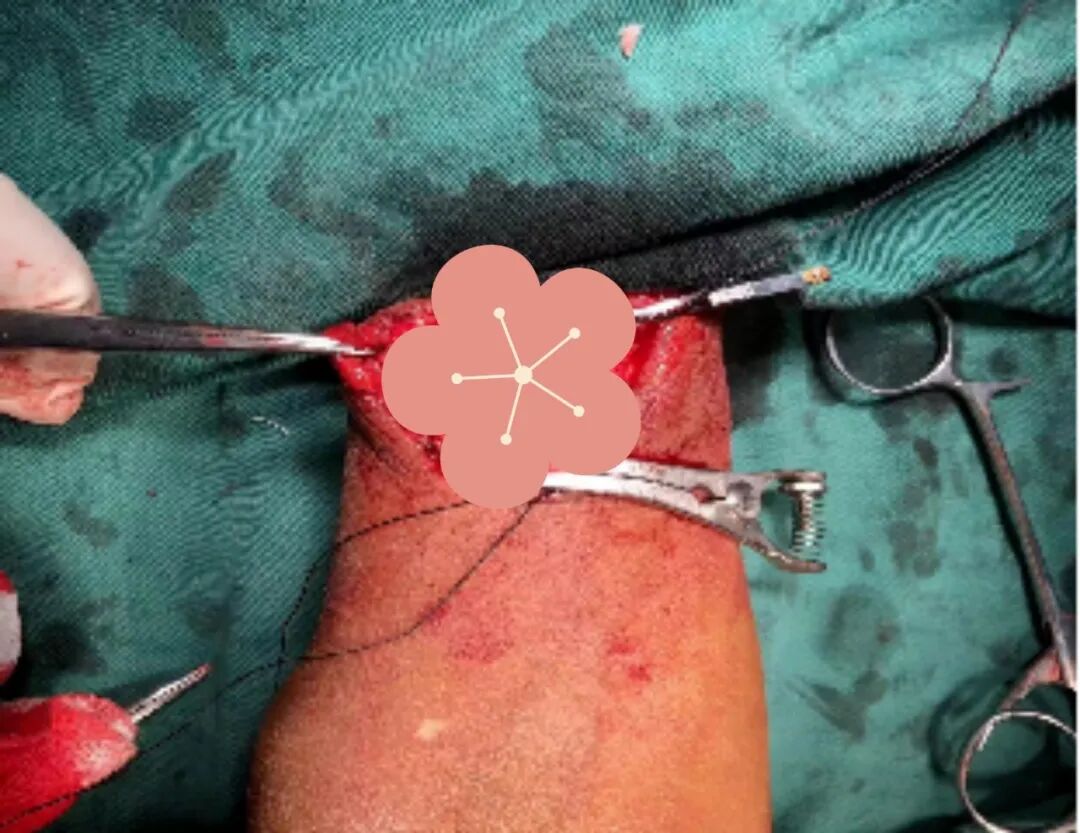

★动静脉内瘘成形术:通过微创手术将患者自身动脉与静脉吻合,使静脉动脉化,满足反复穿刺与充足血流量需求,创伤小、安全性高,是长期透析患者的“首选通路”。

★超声/介入下球囊扩张术:针对内瘘狭窄,超声引导下精准扩张狭窄部位(无需开刀、恢复快);针对深部血管病变,借助DSA血管造影“导航”,清晰定位并处理复杂病变。

此外,科室常规开展动静脉造瘘后球囊扩张、内瘘人造血管成形、内瘘血栓取出、经静脉长期(临时)透析导管置入术等,全面覆盖通路“建立-维护-修复”需求。